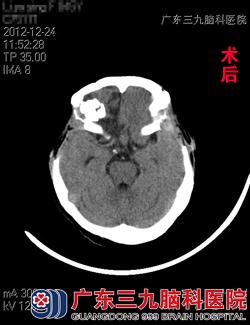

入院查体见黎女士呈深昏迷状态,可以自主呼吸,但呼吸稍深而快,颈软,双肺呼吸音粗,可闻及湿性罗音,四肢对刺痛无明显反应。头颅CT示:右侧额叶挫裂伤并血肿形成,前额跨中线硬膜外血肿,颅骨粉碎性骨折。完善术前检查,跟家属交待病情后,急诊在全麻下行冠切入路颅内血肿清除+双侧额颞顶去骨瓣减压术+气管切开术。术程顺利,术后回ICU继续治疗。术后5周,黎女士得以康复出院,出院时意识康复良好,四肢活动自如,可自行行走。www.999brain.com